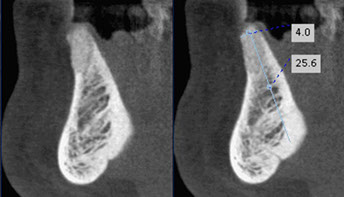

grafted bone in lower incisor area